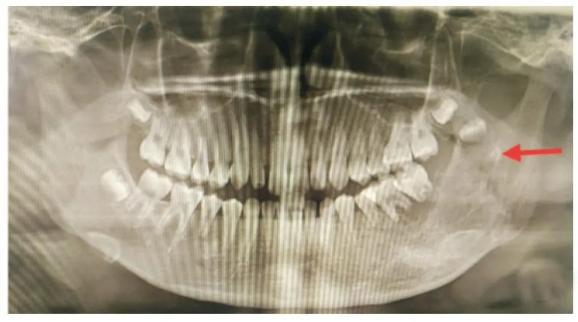

8岁女童龋齿导致颅内脓肿8岁的女孩突然出现高烧、头疼、呕吐等症状,带来医院检查,才发现是孩子左下颌第二门牙出现了龋齿,并且还不断有脓流出。

可怕的是,这部分脓流物已经在孩子的右侧顶枕部已经出现了巨大的占位,需要进行开颅手术,将脓肿切除才行!

小小的蛀牙怎么会危及我们的大脑?这都是因为我们的口腔牙周和面部都有着丰富的血液循环系统,这些系统和颅内是相通的。一旦牙齿被细菌感染,就可能会随血液循环进入大脑,导致脑脓肿或积脓。